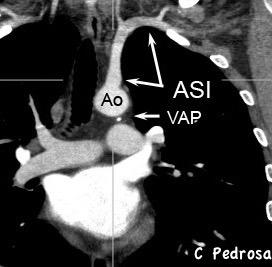

La línea de la arteria subclavia izquierda (ASI) es cóncava en el normal

ASI NORMAL